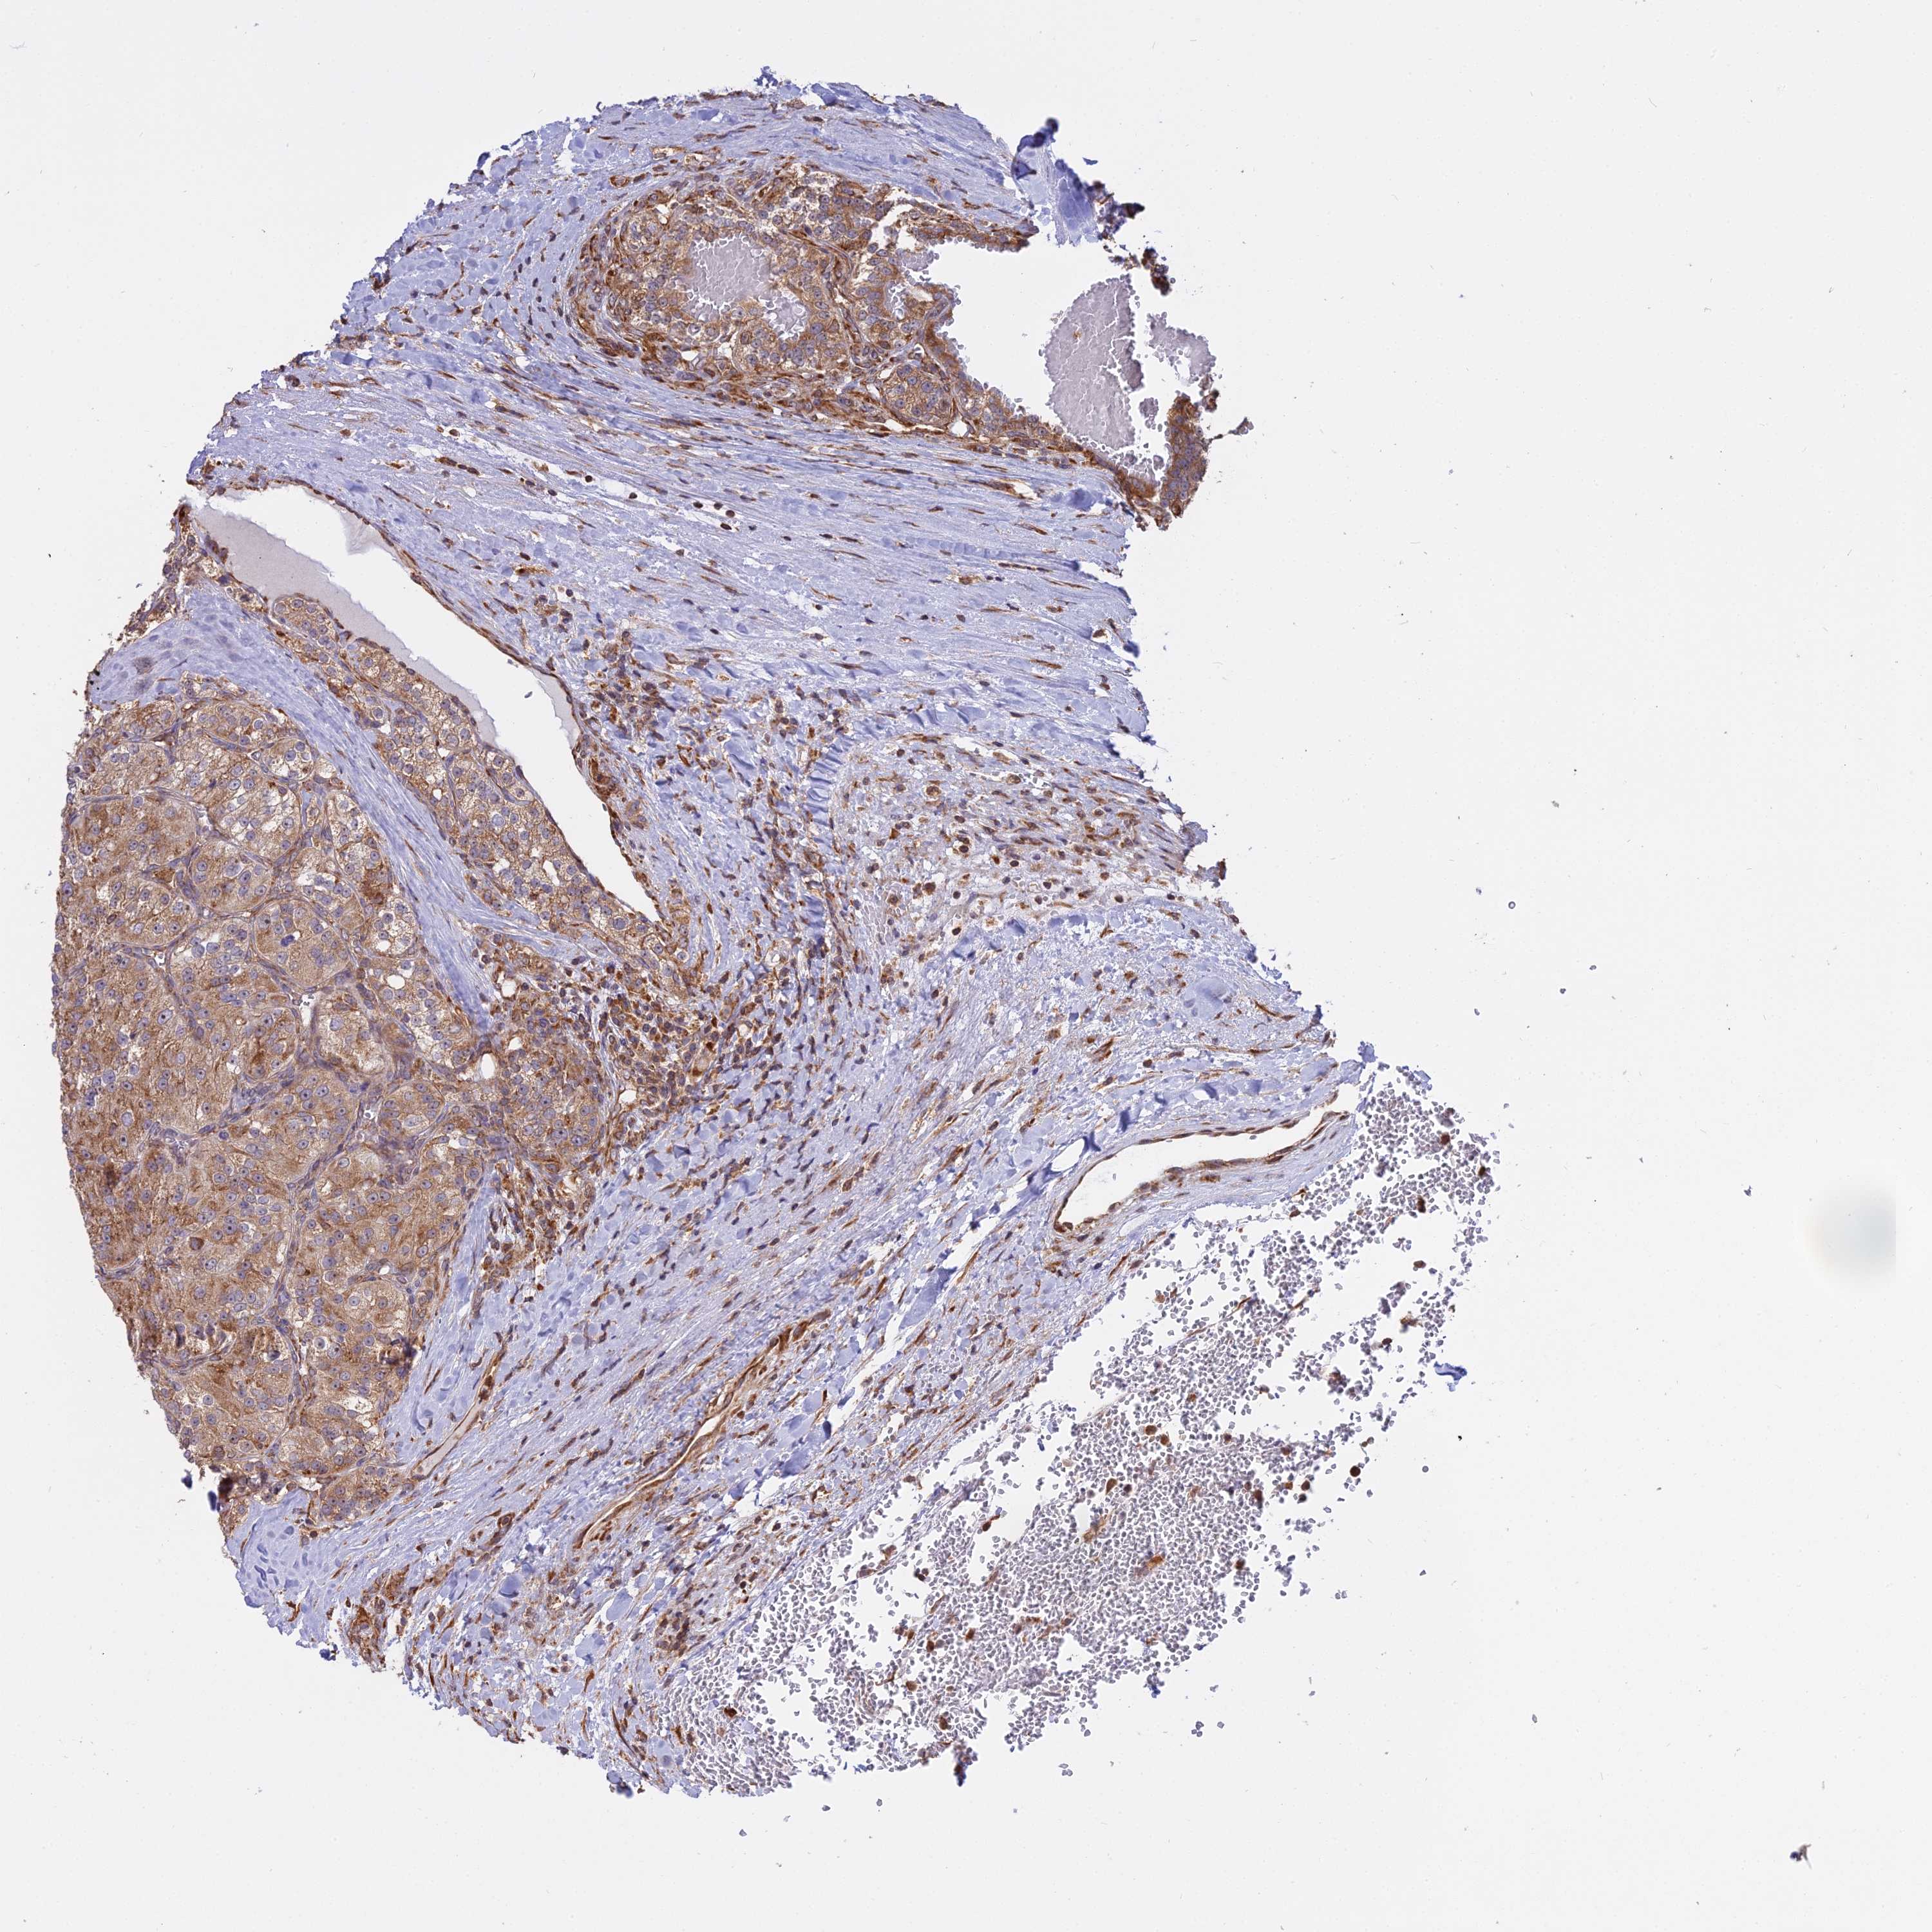

KIDNEY RENAL CLEAR CELL CARCINOMA (VALIDATION) - Interactive survival scatter ploti

The Survival Scatter plot shows the clinical status (i.e. dead or alive) for all individuals in the patient cohort, based on the same data that underlies the corresponding Kaplan-Meier plots. Patients that are alive at last time for follow-up are shown in blue and patients who have died during the study are shown in red.

The x-axis shows the expression levels (FPKM) of the investigated gene in the tumor tissue at the time of diagnosis. The y-axis shows the follow-up time after diagnosis (years). Both axes are complimented with kernel density curves demonstrating the data density over the axes. The top density plot shows the expression levels (FPKM) distribution among dead (red) and alive patients (blue). The right density plot shows the data density of the survived years of dead patients with high and low expression levels respectively, stratified using the cutoff indicated by the vertical dashed line through the Survival Scatter plot. This cutoff is automatically defined based on the FPKM cutoff that minimizes the p-score. The cutoff can be changed by dragging the vertical line or by entering a cutoff value in the square labeled "Current cut-off".

Under the Survival Scatter plot the p-score landscape (black curve; left axis) is shown together with dead median separation (red curve; right axis). Dead median separation is the difference in median mRNA expression between patients who have died with high and low expression, respectively. It is calculated as follows: median FPKM expression of dead patients with high expression - median FPKM expression of dead patients with low expression. This is intended to aid the user in visually exploring custom cutoffs and the associated p-scores and dead median separation.

Individual patient data is displayed and can be filtered by clicking on one or more of the category buttons on the top of the page. Categories describing expression level and patient information include: high, low, alive, dead, female, male and tumor stages. The scale of the x-axis can be toggled between linear and log-scale by clicking on the "x log" button. Mouse-over function shows TCGA ID, patient information and mRNA expression (FPKM) for each patient.

& Survival analysisi

Kaplan-Meier plots summarize results from analysis of correlation between mRNA expression level and patient survival. Patients were divided based on level of expression into one of the two groups "low" (under cut off) or "high" (over cut off). X-axis shows time for survival (years) and y-axis shows the probability of survival, where 1.0 corresponds to 100 percent.

RPL26 is not prognostic in Kidney Renal Clear Cell Carcinoma (validation)

: 2501.78

Average pTPM 2601.9

Number of samples 100